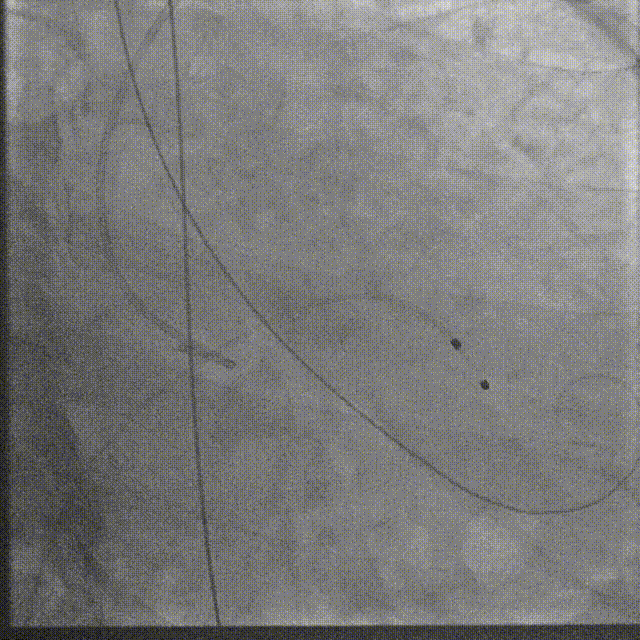

跨瓣

瓣膜系统过弓

在数字减影血管造影(DSA)与经胸超声(TTE)双模影像引导下,学员系统完成经导管主动脉瓣置换术全流程操作:首先建立经皮腹主动脉穿刺入路,随后进行导丝跨瓣定位,继而操控人工瓣膜输送系统,最终实现瓣膜精准释放。训练重点强化三个技术维度:①血管入路建立与并发症预防 ②影像引导下的器械递送路径规划 ③基于实时超声的血流动力学评估。